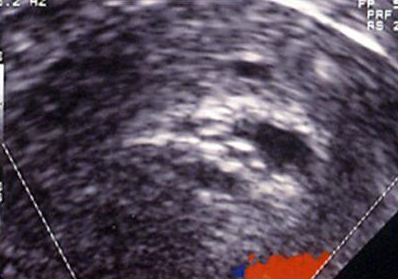

Endomètre type Tamoxifène